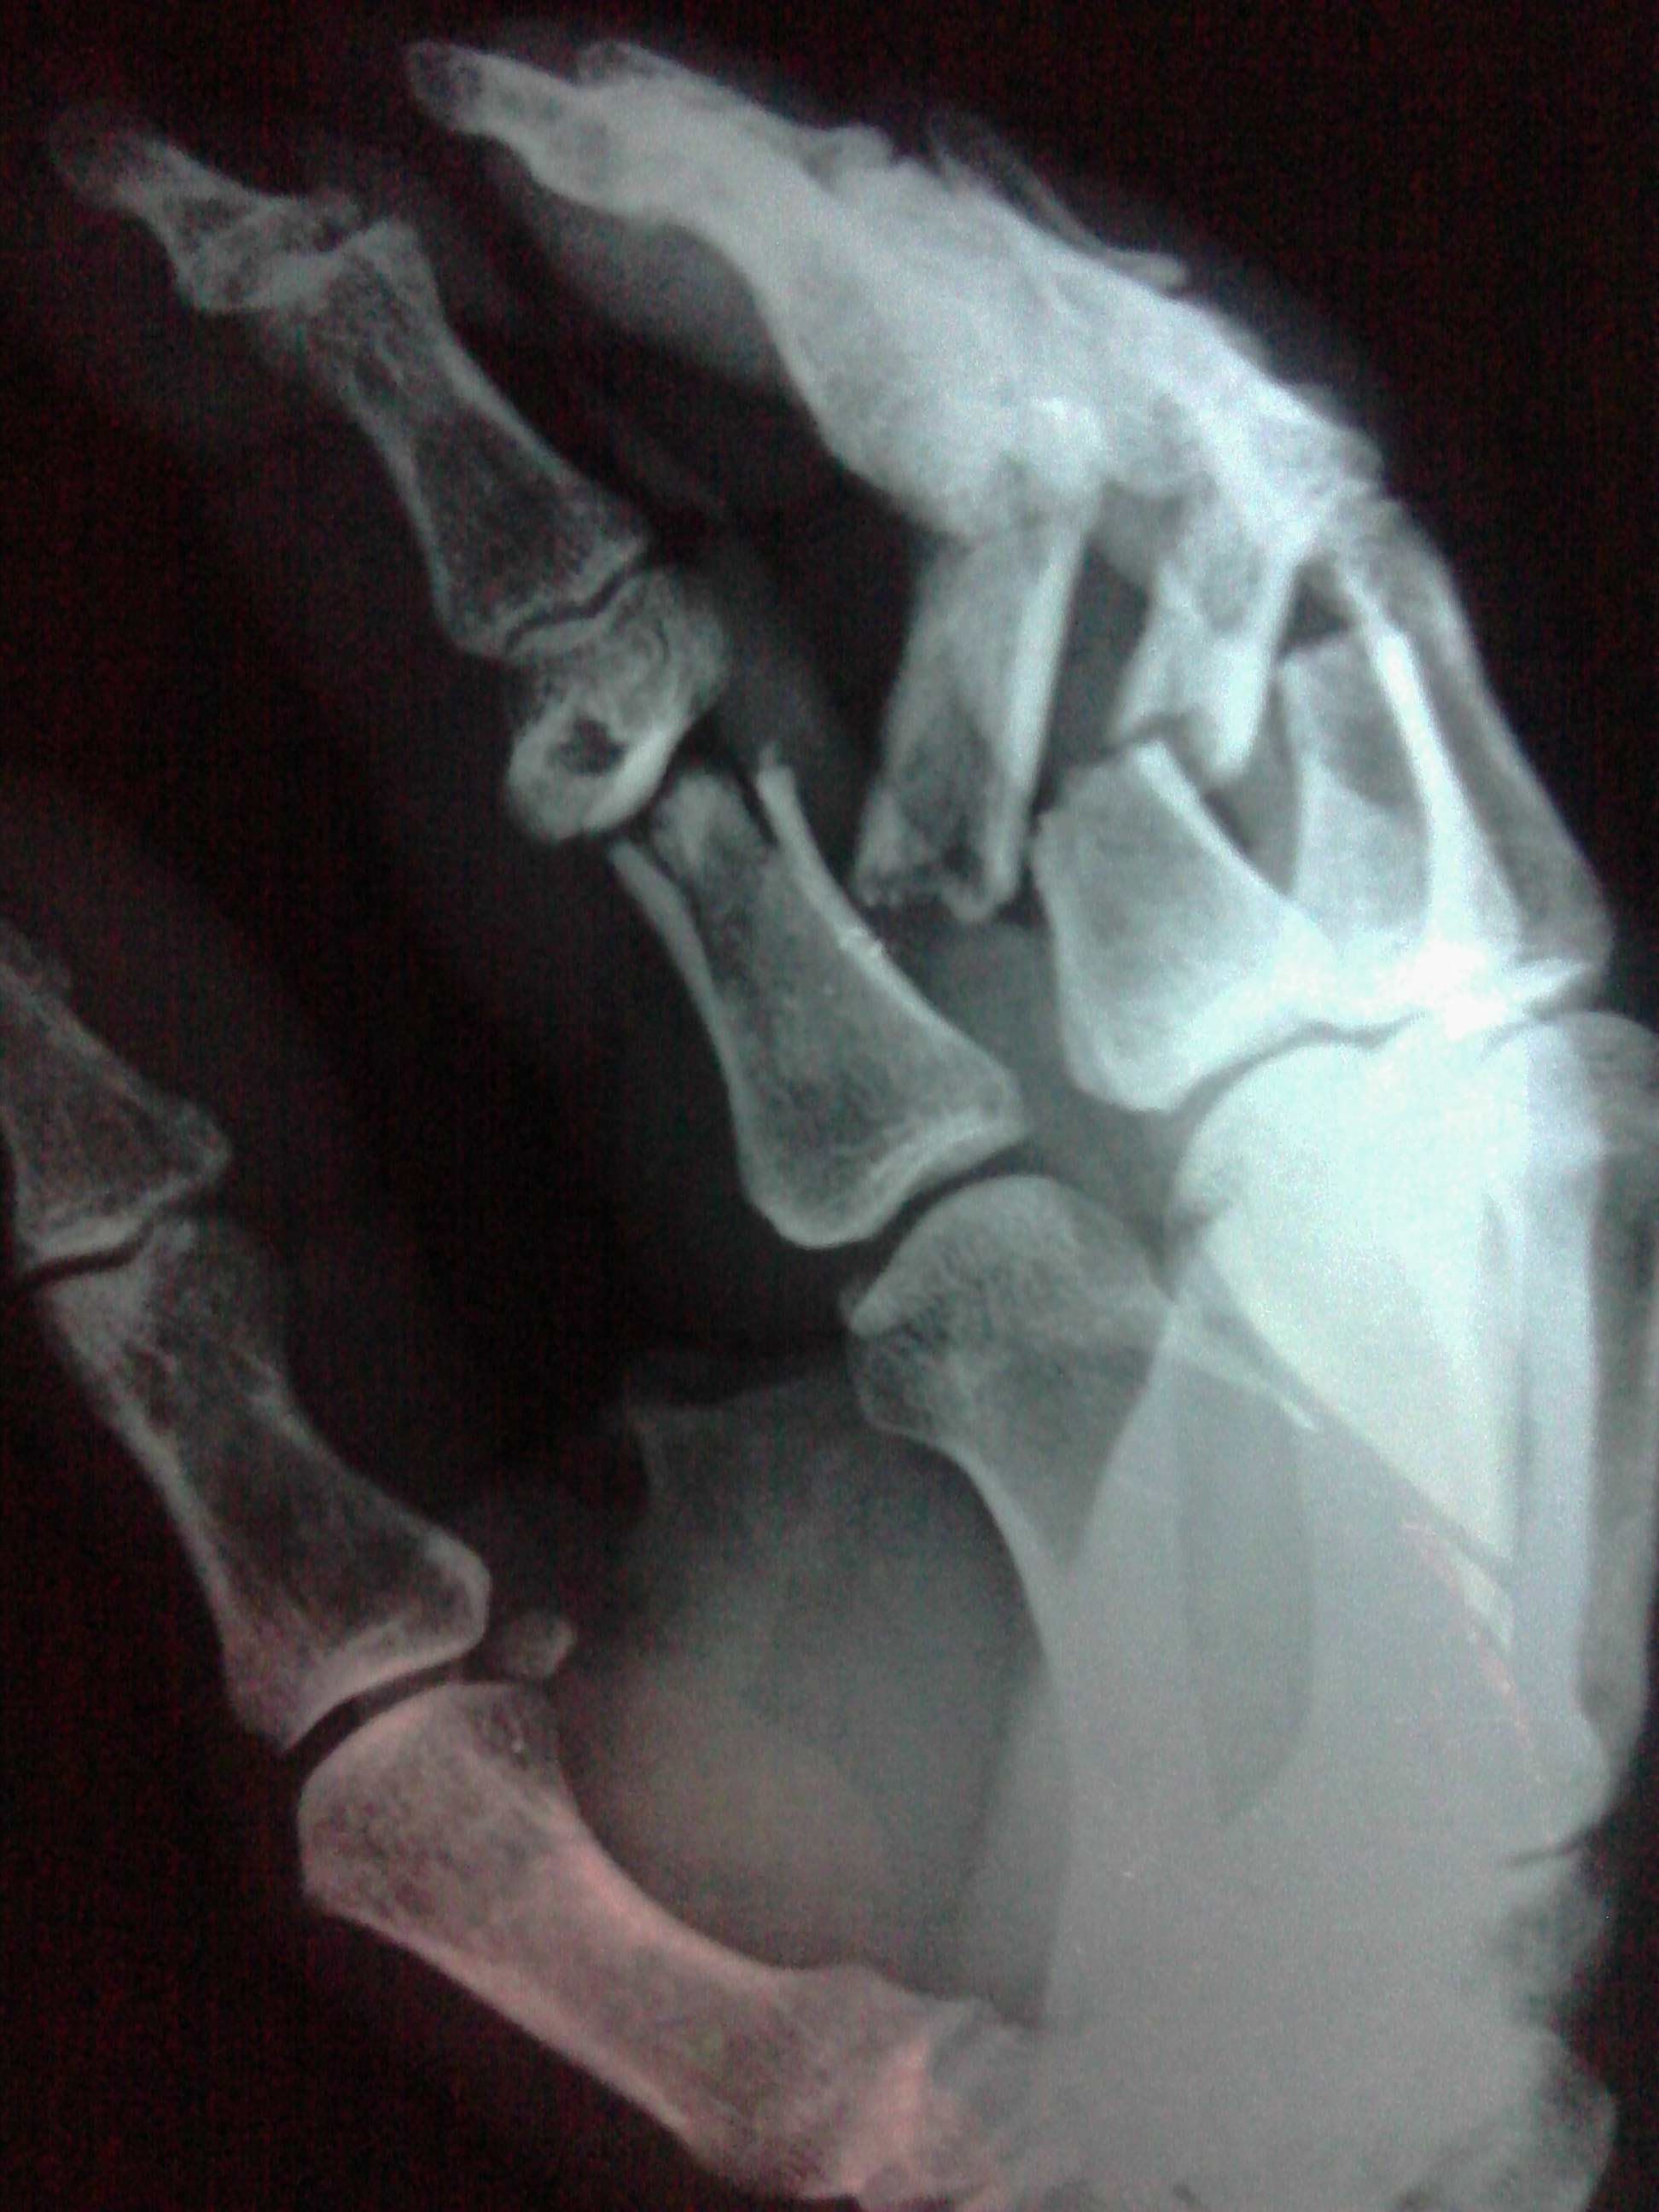

按照你的片子,应该是骨折加钢针固定治疗,基本符合工伤九级。具体看功能影响情况,甚至可以达到更高级别。

没有伤到大拇指关节,最多9级,毫无悬念。严格的来讲,评上10级你就应该庆幸了。